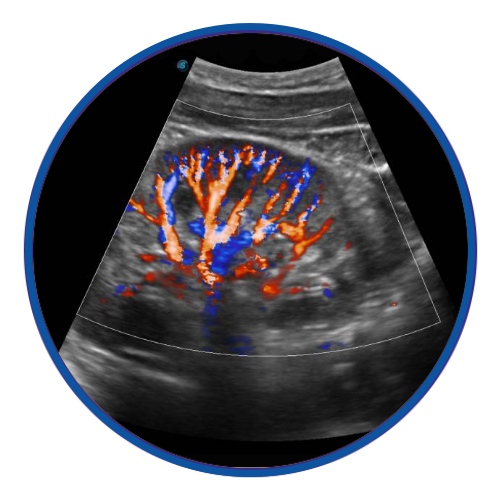

Colour Doppler

Color Doppler uses a computer to convert the Doppler measurements into an array of colors.

Color Doppler uses a computer to convert the Doppler measurements into an array of colors. This color visualization is combined with a standard ultrasound picture of a blood vessel to show the speed and direction of blood flow through the vessel.